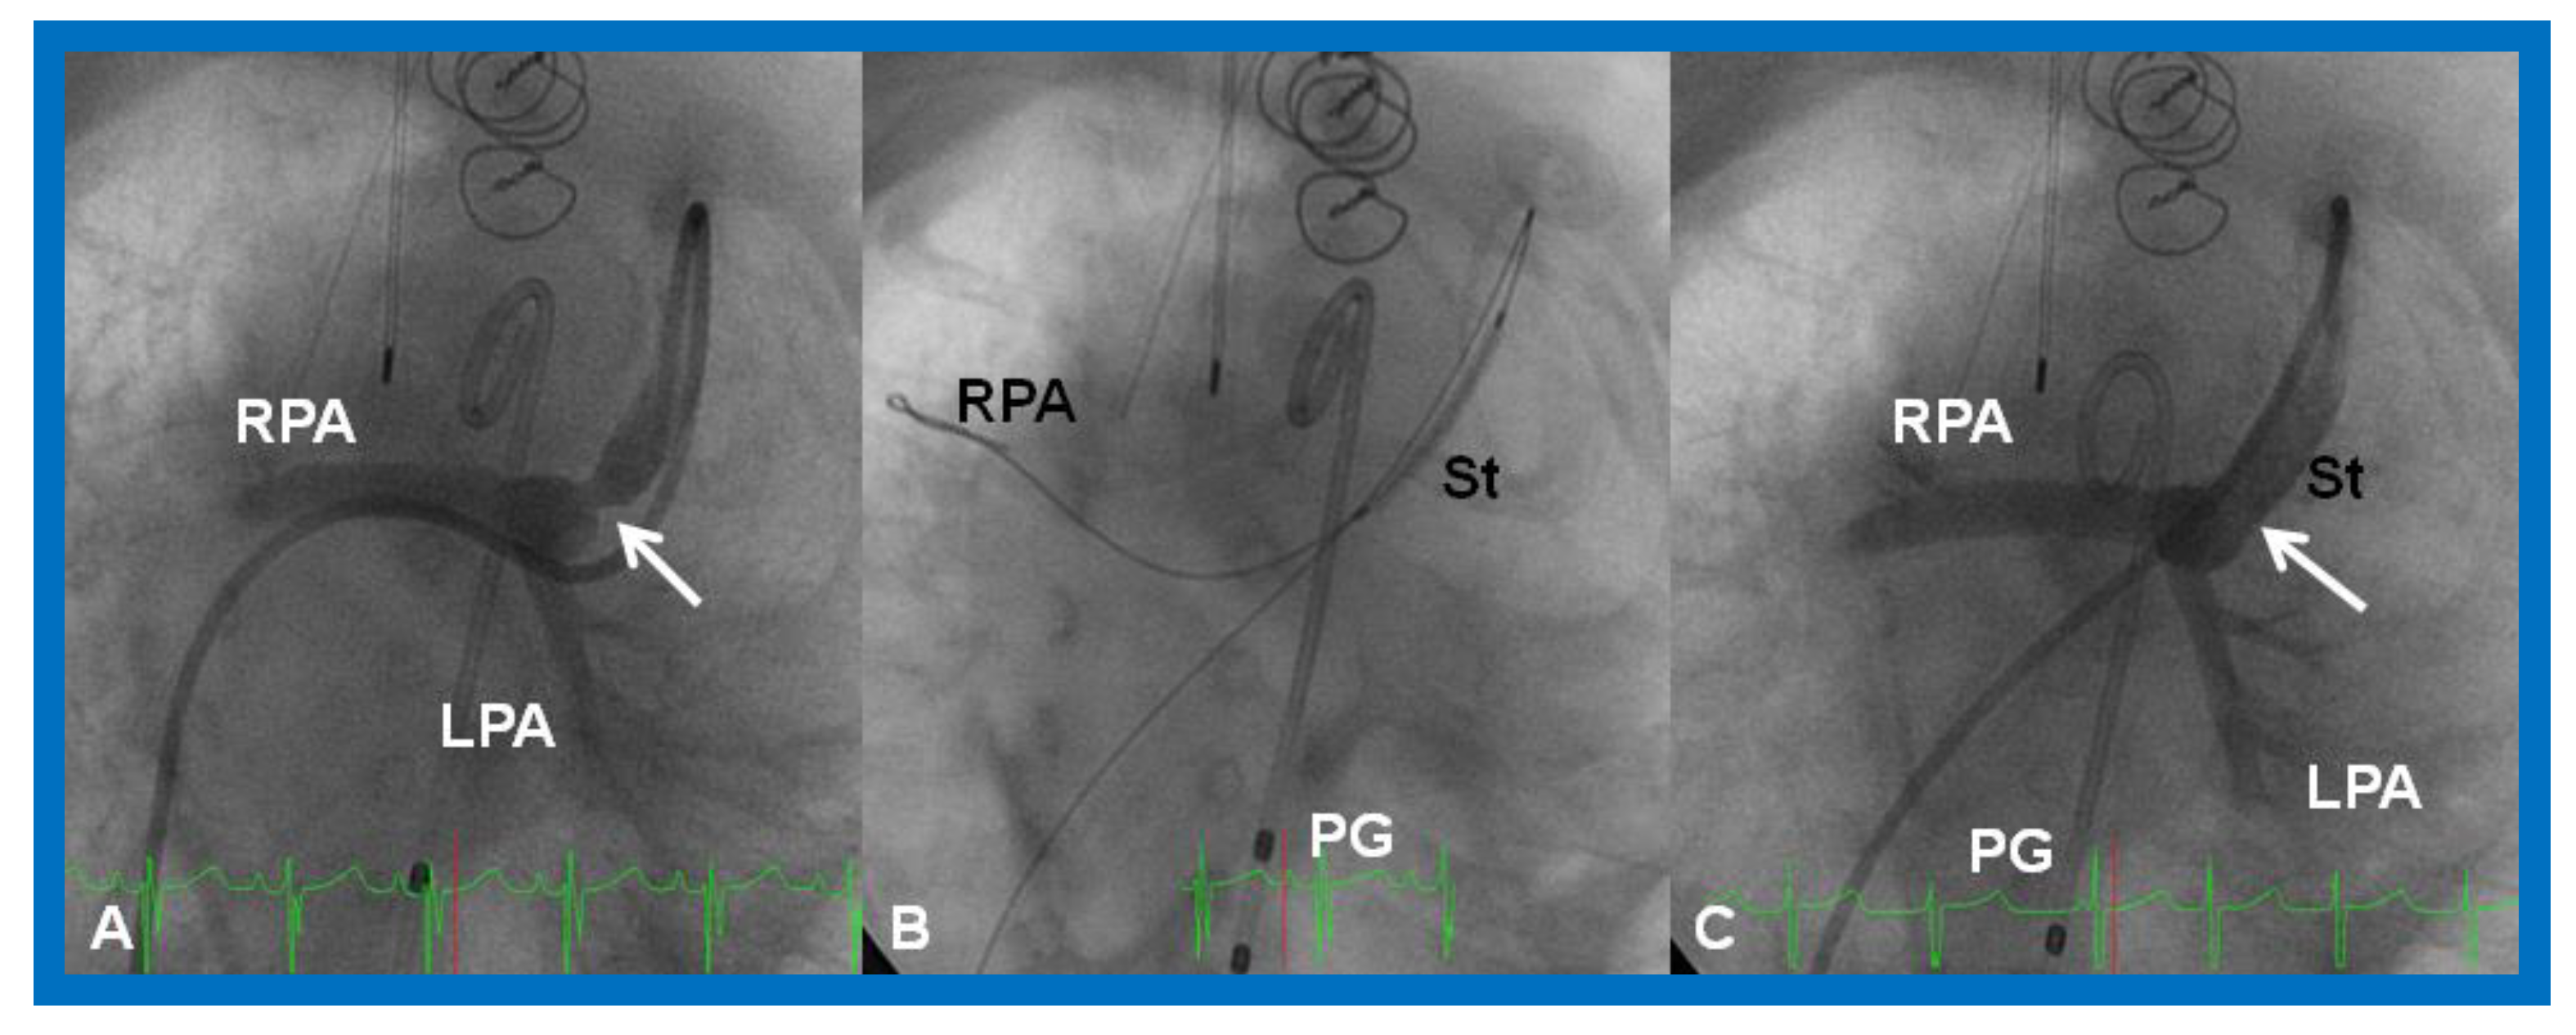

Figure 29.

(A). Cineangiographic frame in a caudal angulation, demonstrating a narrowed (arrow) Sano shunt in a baby with hypoplastic left heart syndrome. (B). A stent (St) catheter is placed across the narrowed site with the guide wire positioned deep into the right pulmonary artery (RPA). (C). Note the wide-open (arrow) Sano shunt after the stent was implanted across the narrowed segment. LPA, left pulmonary artery; PG, pigtail catheter. Reproduced from Reference [58].